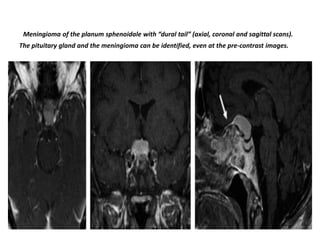

Meningioma of the planum sphenoidale with “dural tail” (axial, coronal and sagittal scans).

The pituitary gland and the meningioma can be identified, even at the pre-contrast images.